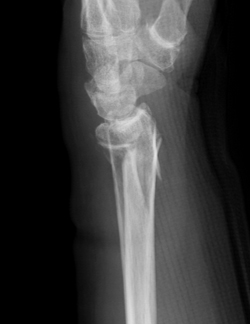

【橈骨遠位端骨折のX線像】

正面像

側面像